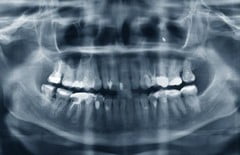

Магнитно-резонансная томография (МРТ) зубов — современный и информативный метод исследования, который используется для диагностики заболеваний зубов, а также мягких и твердых тканей челюсти.

Врачи отмечают, что магнитно-резонансная томография зубов становится все более популярной в стоматологической практике. Этот метод позволяет получить детализированные изображения тканей, что особенно важно для диагностики заболеваний, не видимых при обычных рентгенографических исследованиях. Специалисты подчеркивают, что МРТ помогает выявлять проблемы на ранних стадиях, такие как воспаления или опухоли, что значительно увеличивает шансы на успешное лечение. Однако врачи также предупреждают о необходимости правильной интерпретации полученных данных, так как не все стоматологические проблемы могут быть диагностированы с помощью этого метода. Важно, чтобы МРТ применялся в комплексе с другими методами обследования для достижения наилучших результатов.

Так как многие стоматологические патологии охватывают не только сам зуб и его твердую часть, МРТ назначается для исследования мягких тканей полости рта. Диагностика помогает выявить воспаления оболочек зуба, заболевания зубной пульпы и десен, кистозные образования.

Кроме того, данный вид обследования показан людям, страдающим болезнями сустава нижней челюсти. Полученные снимки томографа позволяют специалистам детально изучить состояние хрящей (изменение положения мениска, поверхностей суставов, повреждение диска сустава). Проведение МРТ зубов также необходимо при имплантации, особенно, если она совмещается с реконструктивной челюстно-лицевой хирургией.

Современная литература по МРТ зубов показывает, что эта методика используется для цефалометрии в ортодонтии и челюстно-лицевой ортопедии, выявления воспаления пульпы зуба, характеристики патологий периапикального и краевого пародонта зубов, выявления кариеса и идентификации нижнего альвеолярного нерва, пораженного

Артрит и другие воспалительные процессыартроз и другие дистрофические поражения челюстной областисиновитразличные травмы, включая полные и частичные вывихи, переломысмещение дискааномалии развитияповреждение, изменение ширины, сдавливание сосудов